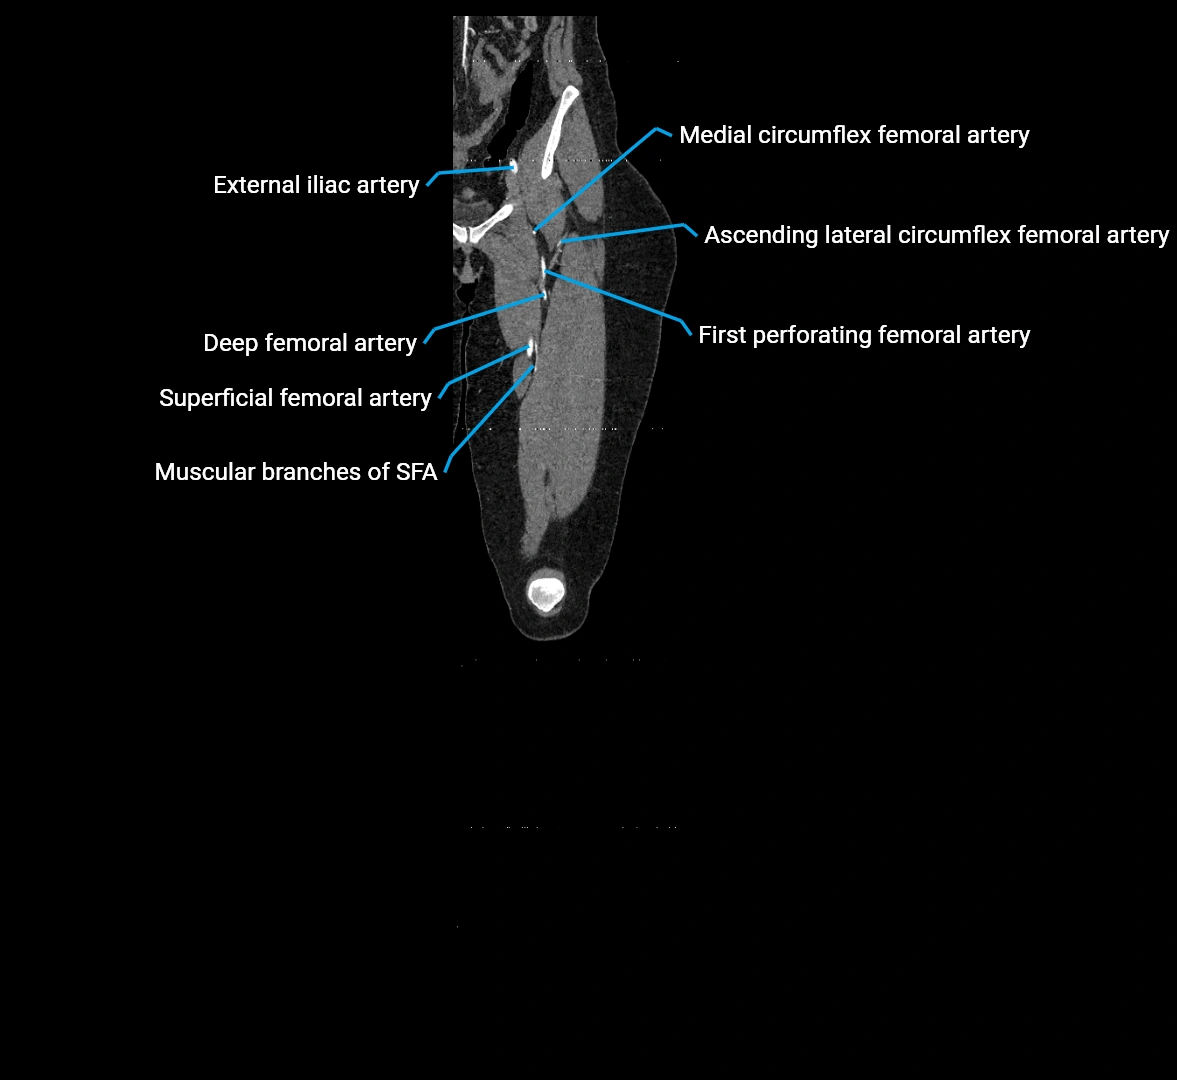

CT images

image